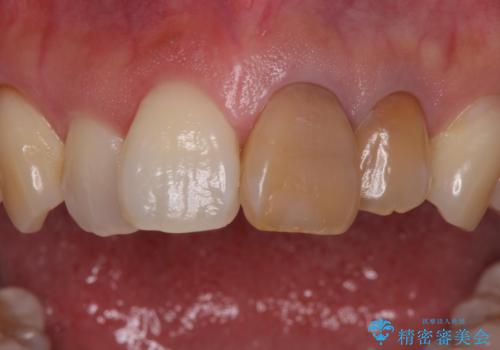

色調はクラウン修復により改善され、歯並びも術前より改善されたことで大変喜んでいただけました。